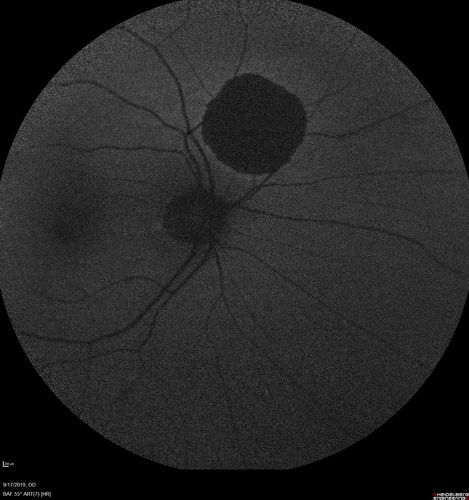

Congenital Hypetrophy of the Retinal Pigment Epithelium (CHRPE)

63 year old female with normal vision and CHRPE lesion in the right eye.